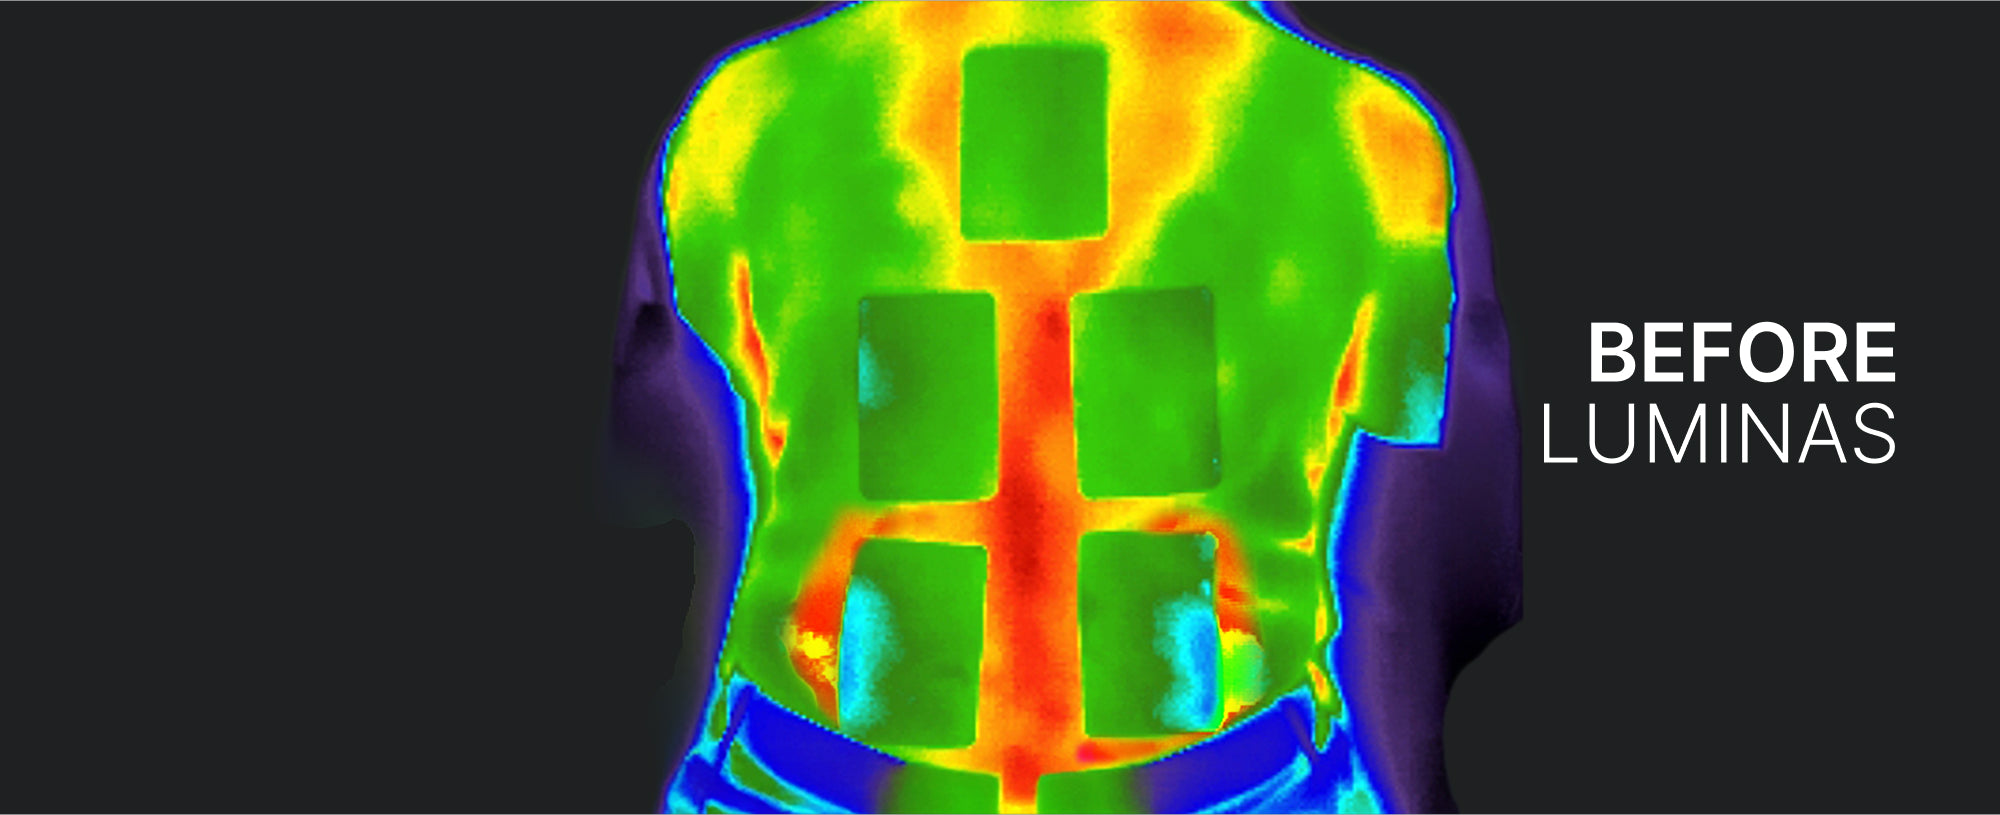

Reduced Inflammation For 94% of Patients!

Using digital infrared thermography, skin temperature (inflammation) was notably reduced.